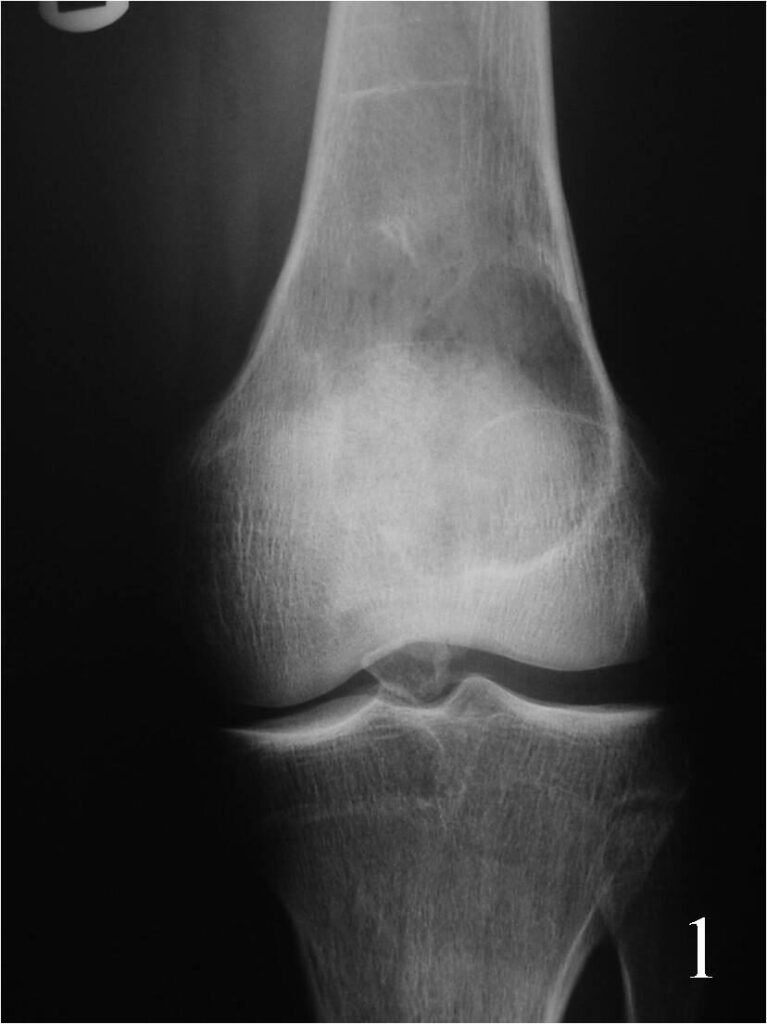

- Geographic well circumscribed lesion usually with thin rim of reactive sclerosis and no matrix mineralization/calcification arising eccentrically in metaphysis (Fig. 1)

Fig. 1 AP Xray of the knee showing an eccentric well circumscribed geographic and expansile lesion on the distal meta-ephyphiseal area of the femur